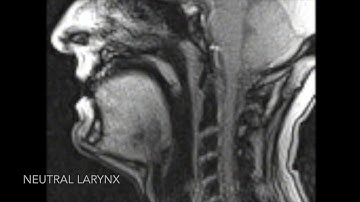

Final alignment result of real-time MRI video, vocal tract contours, and EMA sensors